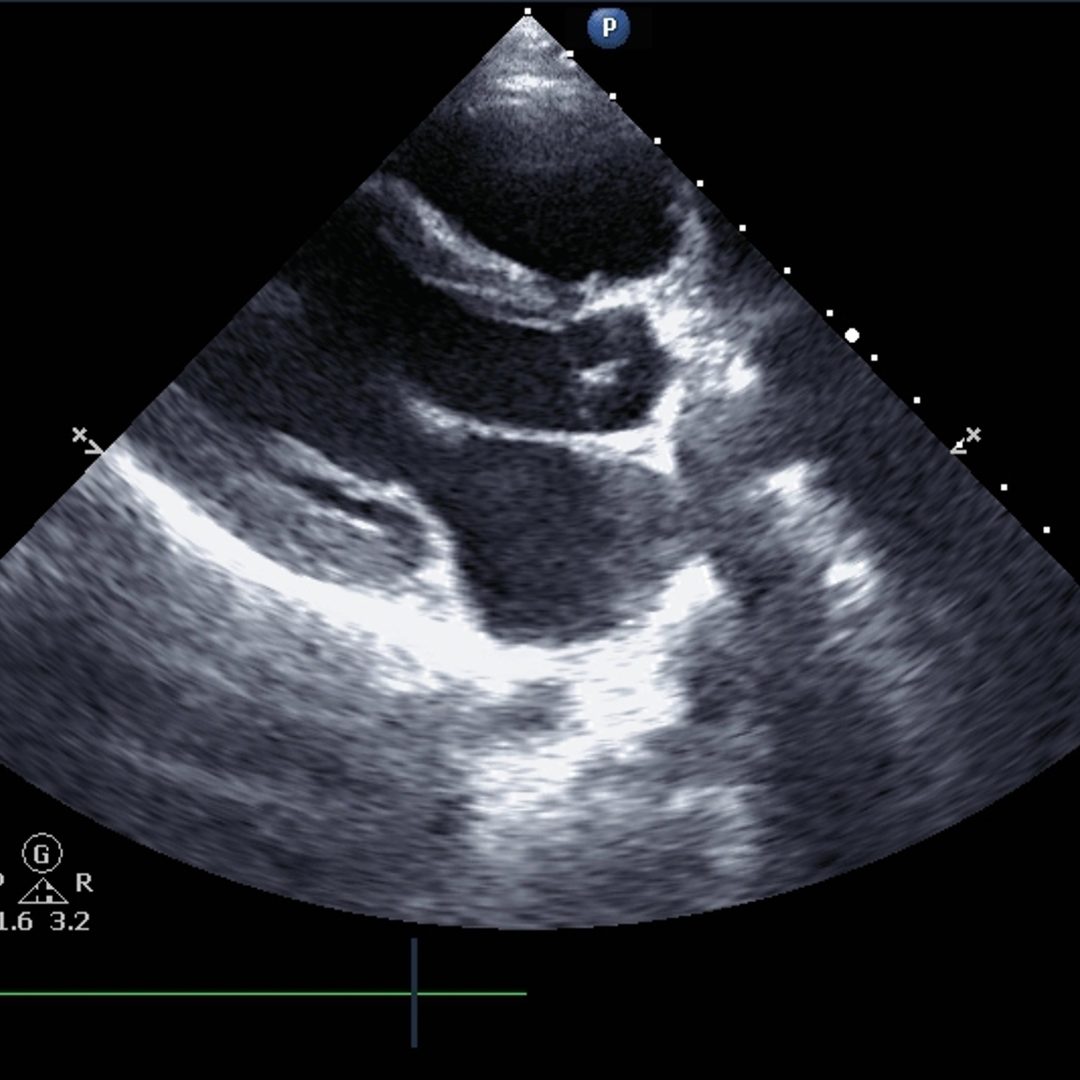

心エコー検査(超音波検査)

動悸を評価する検査の一つとして、心エコー検査(超音波検査)があります。

これは、心臓の構造と機能を視覚的に評価し、潜在的な心疾患を診断するための重要な検査です。

心エコー検査は、高周波の音波(超音波)を使用して心臓の動きを映像化し、心臓のサイズ、形、心室の壁の動き、心臓弁の動きを評価します。

これにより、心筋症、弁膜症、先天性心疾患などの心疾患を診断することができます。

これらの疾患は、しばしば動悸の原因となります。

また、心エコー検査は、心臓のポンプ機能(駆出率)を評価するのにも使われます。

これは、心臓が血液を体にどれだけ効率的に送り出しているかを示します。

心不全の患者様では、この駆出率が低下していることがあります。

心エコー検査は、動悸がある場合の診断プロセスの一部として非常に有用な検査であり、心臓の構造的な異常や機能的な問題を確認することができます。

この検査により、医師は動悸の根本的な原因を特定し、最適な治療戦略を立てることが可能になります。